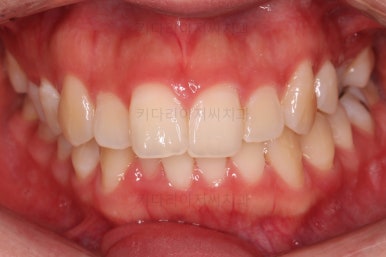

1. 초진

초진 시 입안의 모습입니다.

전반적으로 치열이 삐뚤고요.

위아래 중앙선이 약간 틀어져 있는데 많이 심한 편은 아니고요. 윗니가 배열된 U자 형태를 보면 아랫니보다 좁은 형태로 "악궁이 좁은" 상황이었습니다.